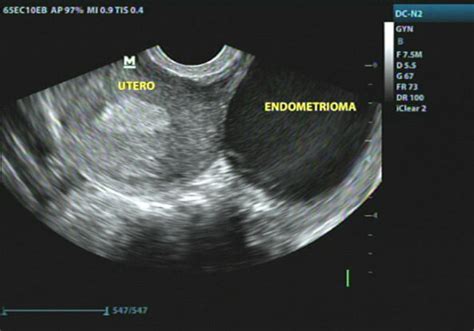

La ecografía transvaginal es la prueba diagnóstica principal y de primera línea para el estudio de la endometriosis ovárica. Esta técnica permite visualizar quistes con características muy típicas, como un contenido homogéneo y paredes engrosadas, sin la presencia de septos. Se considera la técnica más accesible y eficaz para la identificación de endometriomas, con una eficiencia y especificidad reportadas de hasta el 88% y 90%, respectivamente.

El endometrioma típico se presenta ecográficamente como una formación quística redondeada u ovoide, unilocular, con paredes gruesas y regulares. Su contenido se describe como hipoecoico homogéneo, a menudo denominado “vidrio esmerilado”, debido a la presencia de fluido denso homogéneo. Típicamente, estos quistes carecen de septos, presentan una mala vascularización periférica y ausencia de vascularización central, sin proyecciones papilares o áreas sólidas. La frecuencia de esta apariencia típica se estima entre el 73% y 82% de los casos de endometriomas.

Es fundamental, al detectar un endometrioma mediante ecografía, evaluar la posible existencia de adherencias pélvicas y buscar signos de endometriosis profunda y adenomiosis. Esta evaluación integral permite determinar la extensión de la enfermedad en toda la pelvis, lo cual es crucial para un manejo adecuado de la paciente.